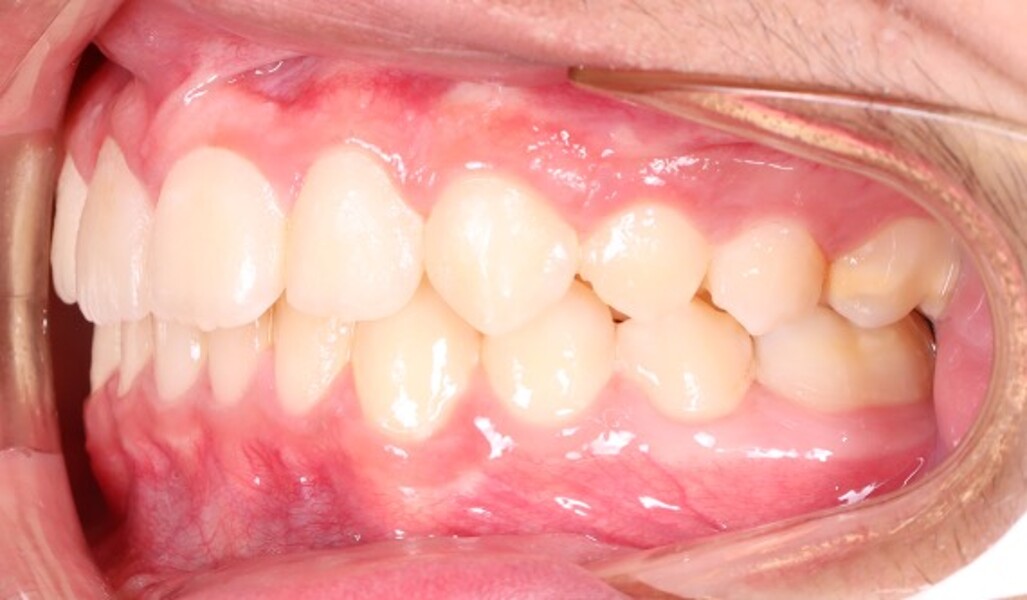

The final records demonstrated (Figs. 7–9; Table 2):

stable bilateral Class I molar and canine relationships;

normalised overjet and overbite;

well-aligned dental midlines coinciding with the facial midline;

fully developed, symmetric and parabolic dental arches; and

absence of root resorption and satisfactory root parallelism.

Radiographic evaluation showed symmetrical mandibular structures and normally seated condyles, and no pathology was detected. The findings showed correction of the skeletal Class II relationship primarily through improvement in mandibular position, as well as showed normalisation of overjet and overbite and establishment of a more balanced skeletal and dental relationship.